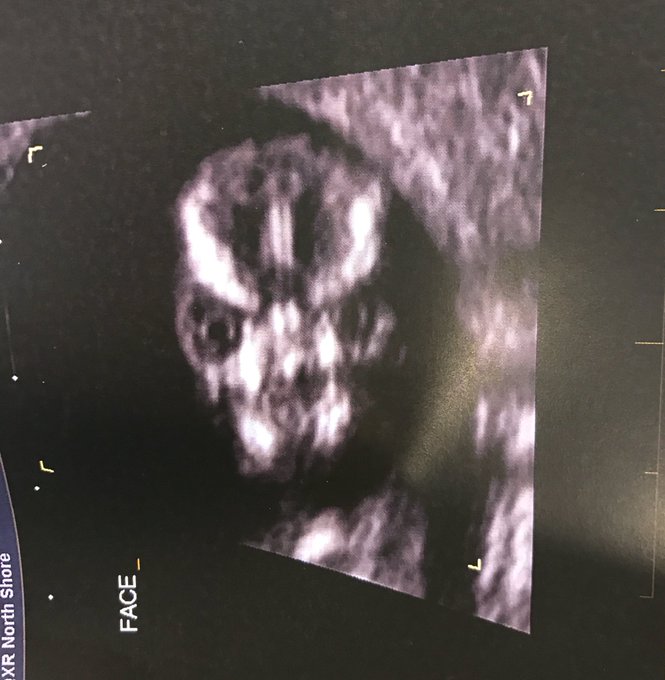

Según escribió Sharni Turner en la red social, el técnico encargado del procedimiento diagnóstico decidió hacer una toma frontal de la cabeza del feto, que según ella, resultó ser "lo más aterrador" que jamás hubiera visto.

La inusual ecografía rápidamente se convirtió en un éxito viral y provocó cientos de comentaros de quienes, con humor, especularon sobre qué tipo de 'criatura' está esperando Turner.

Algunos compararon al bebé con una robot 'Transformer', con el antagonista de la película de terror británica 'Siniestro' y hasta con Lord Voldemort, enemigo principal de Harry Potter en las novelas fantásticas.

Finalmente, y luego de las graciosas especulaciones de los usuarios, Sharni publicó una fotografía más amigable del pequeño. "Afortunadamente es mucho más lindo de lado", afirmó.